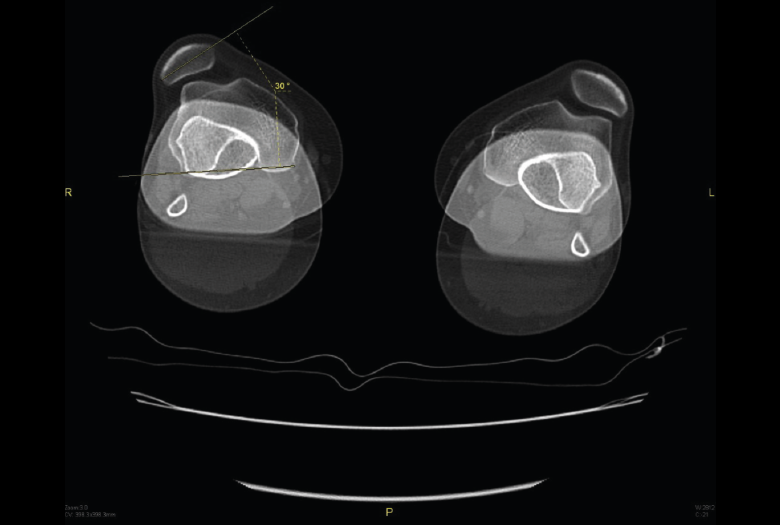

5.1. TA-GT (tuberosidad tibial anterior-garganta de la tróclea)

En pacientes sintomáticos con inestabilidad rotuliana, la TAC es útil para medir la TA-GT(10). La distancia TA-TG es una medida radiológica propuesta por Goutallier y Bernageau que sirve para cuantificar el ángulo Q. Consiste en medir la distancia en milímetros de la tuberosidad tibial anterior a la garganta de la tróclea proyectadas sobre una línea que pasa por los bordes posteriores de ambos cóndilos femorales, superponiendo 2 cortes axiales de TAC. Es una medida fiable y reproducible pero poco precisa, con un margen de error de más de 4 mm. La distancia TA-GT es mayor de 20 mm en el 56% de las inestabilidades rotulianas y tan solo en el 3% de la población sana(11)(Figura 28).

Figura 28. Corte axial de tomografía axial computarizada con superposición de imágenes con rótula y parte posterior de cóndilos y tuberosidad tibial anterior, que nos permite medir la distancia TA-GT, en condiciones normales hasta 2 cm.

5.2. Balance rotuliano

Mide la inclinación de la rótula en relación con el borde posterior de los cóndilos femorales (Figura 29).

Figura 29. Corte axial de tomografía axial computarizada con superposición de imágenes con rótula y parte posterior de cóndilos y tuberosidad tibial anterior, que nos permite medir el tilt o balance rotuliano, en condiciones normales hasta 20°.